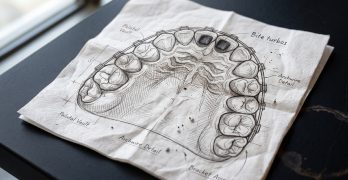

Brackets Damon Ultima y Protocolo de Bite Turbos y Elásticos en una Clase II Severa

Hoy traemos un artículo del Journal of Digital Orthodontics llamado Management of Anterior Deep Bite and Posterior … [Leer más...] acerca de Brackets Damon Ultima y Protocolo de Bite Turbos y Elásticos en una Clase II Severa

Desarticuladores en Ortodoncia, métodos y aplicaciones.

En la ortodoncia cuando estamos arreglando la maloclusión, a veces los dientes de arriba chocan con los de abajo de una … [Leer más...] acerca de Desarticuladores en Ortodoncia, métodos y aplicaciones.